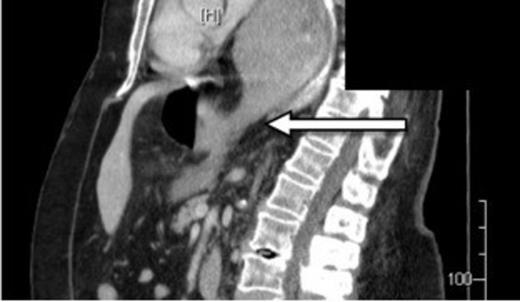

A 73-year-old Caucasian woman presented to the emergency department with 2-day history of vomiting and vague abdominal pain. Her background history included asymptomatic hiatus hernia, morbid obesity (BMI of 35.7), polymyalgia rheumatica, previous laparoscopic cholecystectomy, hypercholesterolaemia and hypertension. Regular medications included prednisone, amlodipine and cilazapril. On presentation she was tachycardic at 110 beats/min with otherwise normal vital signs. Her abdomen was generally tender but without any localised peritonism. Initial laboratory investigations on admission showed a leukocytosis (WCC of 13.8 x 109/L). Routine X-ray (figure 1) and subsequent (CT) scan (figure 2) both revealed a large strangulated paraoesophageal hernia. Radiographic changes (figure 3) were seen with gas within stomach wall, suggestive of gastric necrosis.

CT showing gas within stomach wall (arrow) suggestive of gastric necrosis